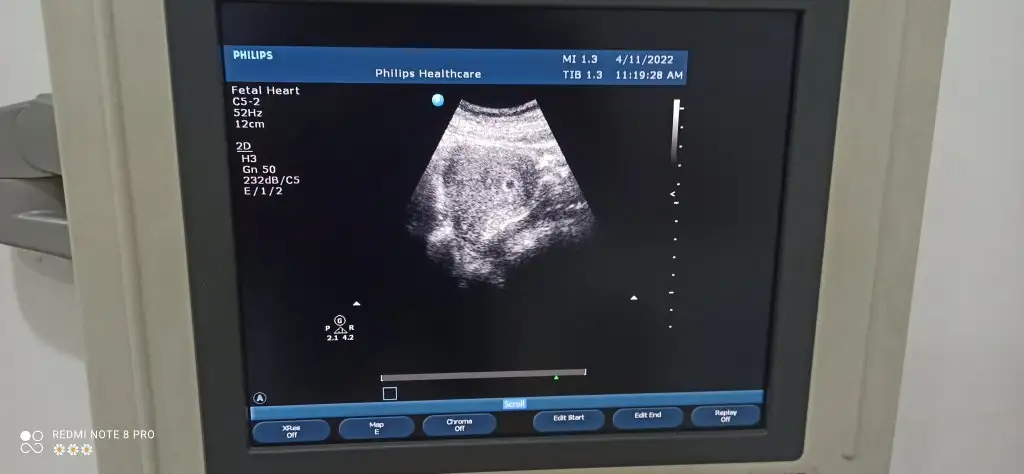

O 12 cm cihazla ilgili galiba kese ölçüsü almamış. Kesenin içinde beyaz yer minnoş susamın. Sağlıkla büyüsünArkadaşlar kesem bu şekilde doktor çok bir bilgi vermedi sağlıklı on gün sonra kalp atışına gelmelisin dedi sadece anlayanlar bakabilir mi kenarda 12 cm yazıyo normaldir demi 5 haftalık oldu bugün

Ay teşekkür ederimO 12 cm cihazla ilgili galiba kese ölçüsü almamış. Kesenin içinde beyaz yer minnoş susamın. Sağlıkla büyüsün![]()